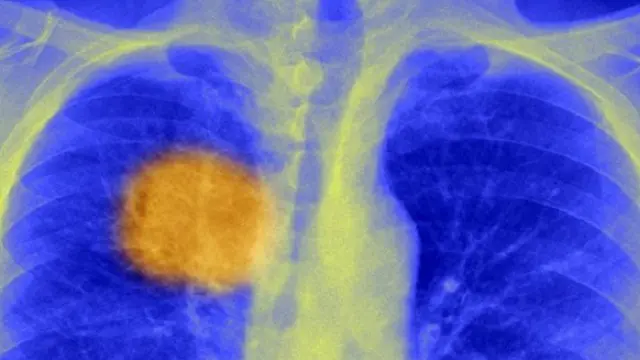

صدر الصورة، SPL

يعتقد علماء أنهم توصلوا إلى أسلوب لـ"توجيه" جهاز المناعة لكي يقتل السرطان، وهو أسلوب ينطبق عليه مصطلح "عقب أخيل"، الذي يشير إلى نقطة ضعف مميتة يؤدي استهدافها إلى انهيار صاحبها مهما بلغت قوته.

فقد طور الباحثون بجامعة كوليدج لندن طريقة لرصد علامات فريدة داخل الورم – "عقب أخيل" الخاص به – بما يسمح للجسد باستهداف المرض.